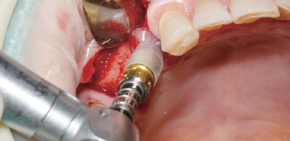

Caso clínico utilizando fresa de obtención Ø3.5/4.0.

by Dr. Soohong Kim, DDS, Ph.D

Se realizó fresado a 300 RPM luego de marcar posición del sitio de implante y obtención.

La pantalla de silicona se llevó a contacto íntimo con los distintos niveles de hueso para prevenir la pérdida de limalla de hueso.

El hueso obtenido se observa con facilidad a través de la pantalla de silicona transparente.

El hueso se transfirió a un frasco luego de desensamblar la pantalla de silicona y stopper.

La cantidad de hueso fue mucho más que la esperada.

Luego de la instalación del implante, se conectan los pilares de cicatrización y se lleva a cabo la regeneración ósea en el defecto.